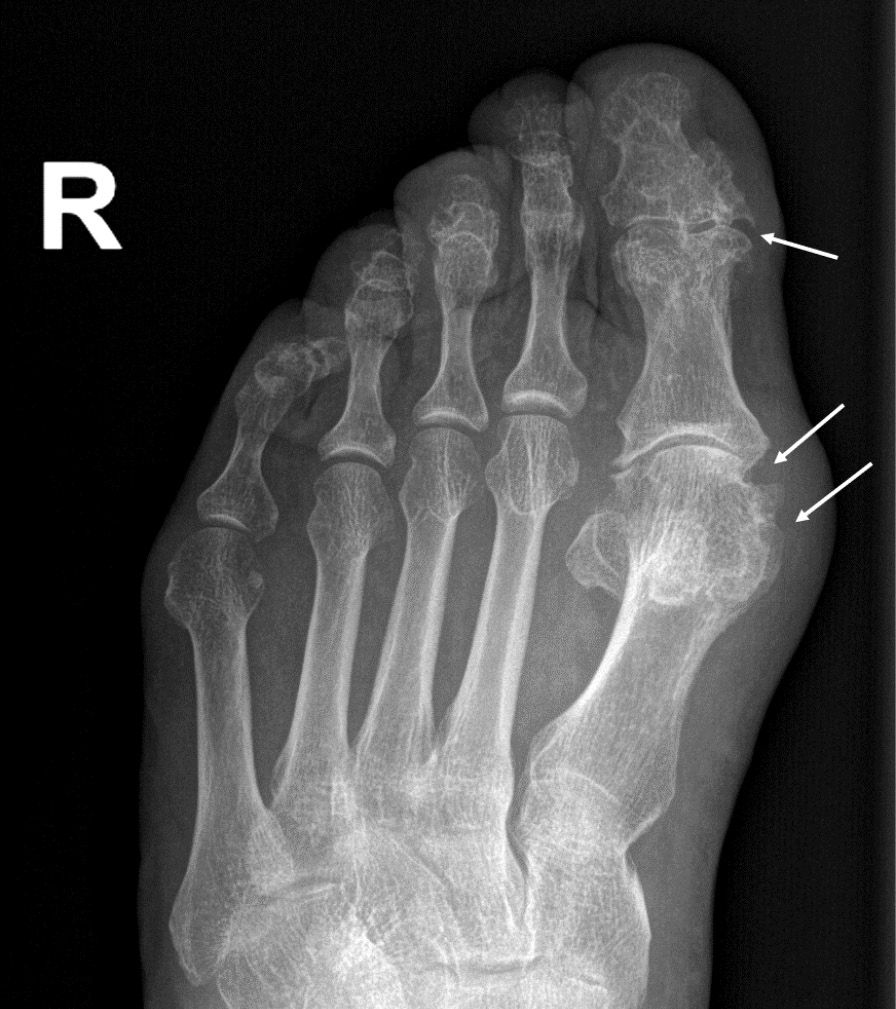

При компьютерной томографии органов грудной клетки данных за «свежие» очаговые и инфильтративные изменения не получено. Увеличения лимфатических узлов подмышечных областей, средостения, корней легких не выявлено. Отмечался усиленный грудной кифоз, обызвествление передней продольной связки, на всем уровне исследования определялись передне-боковые спондилофиты, а также анкилоз большинства реберно-поперечных суставов. По данным рентгенографии кистей (рис. 1, 2) и стоп (рис. 3, 4) диагностированы признаки эрозивного артрита, анкилоз суставов запястья. По данным МРТ крестцово-подвздошных суставов (КПС) определялся неравномерный анкилоз КПС, хрящи по суставным поверхностям неравномерной толщины, примерно на половине протяжении сустава отсутствуют, «суставной промежуток» облитерирован. Неравномерность и нечеткость контура суставных поверхностей за счет множества краевых эрозий справа, единичных – слева, с наличием остеокластоза, в нижнем отделе слева по смежным отделам определяются участки трабекулярного отека, данная находка клинически интерпретирована как двусторонний активный сакроилиит (рис. 5, 6).

Рис. 3. Рентгенограмма правой стопы в прямой проекции. Краевые эрозии суставных поверхностей первого плюсне-фалангового сустава и межфалангового сустава I пальца (стрелки), сужение суставных щелей. Вальгусная деформация I пальца стопы

В возрасте 40 лет присоединились жалобы на симметричные воспалительные боли в лучезапястных суставах и мелких суставах кистей, резкое снижение объема движения в лучезапястных суставах. При осмотре пациента выявлено: число болезненных суставов – 7, число припухших суставов – 4, положительный симптом поперечного сжатия кистей и стоп, ульнарная девиация мелких суставов стоп. Резко сниженный объем движения в лучезапястных суставах обеих кистей. По данным рентгенологического обследования зафиксированы типичные изменения для РА: резкое неравномерное выраженное сужение суставных щелей, субхондральный склероз в лучезапястных суставах, анкилоз в суставах запястья, пястно-запястных, пястно-фаланговых и межфаланговых суставах. Краевые эрозии оснований основных фаланг двух пальцев; участки кистовидной перестройки костной ткани. Локальное утолщение мягких тканей. При лабораторном обследовании пациента отмечен положительный ревматоидный фактор, высокий титр антицитруллинированных антител, повышение острофазовых белков.